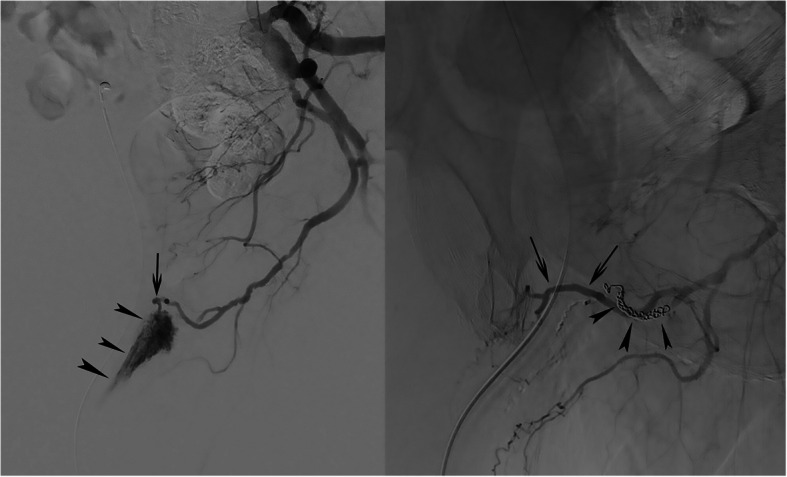

Fig. 1.

a Selective left internal iliac artery angiography. Contrast injection revealed a direct fistulous communication between the bulbourethral artery (arrow) and the corpus spongiosum (arrowheads). b Completion selective angiography after coil (arrowheads) and Onyx embolization. Contrast injection shows the disappearance of the arteriospongious fistula and a patent dorsal penile artery (arrows)